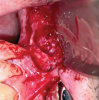

Three months later, a cone-beam computed tomography (CBCT) scan revealed the indication of a MSA due to a pneumatized right maxillary sinus with residual bone height of 2.5 mm and two Underwood septa (Figure 2). Prior to the MSA procedure, based on scientific protocols that suggest smoking cessation for at least 10 days before and after surgery,6,11 the patient was strongly advised to cease his smoking habits due to the risk of bone graft failure.

Fig 2. Preoperative CBCT scan showing a sagittal section of pneumatized right maxillary sinus in edentulous site No. 3.

Figure 2